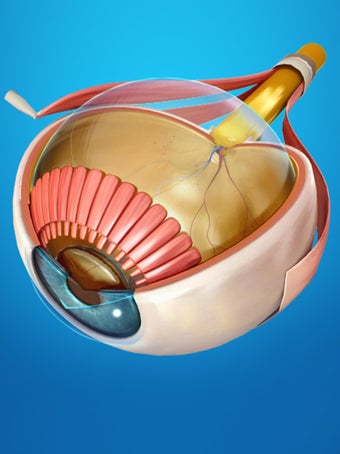

Изучите в деталях человеческий глаз и его анатомию с помощью этого простого в использовании бесплатного приложения для Android. Он позволяет масштабировать и вращать на 360° вокруг высокореалистичной 3D-модели глаза, а также рисовать на экране или прослушивать звуковое произношение каждого термина.

Вы можете выбрать X- просмотр луча, скрытие и отображение отдельных частей глаза, а также рисование или белый цвет на экране и обмен снимками экрана, звуковое произношение для всех анатомических терминов и многое другое.

Каждая часть разделена на отдельный вид, где вы можете можно увидеть название детали и ее расположение на глаз.